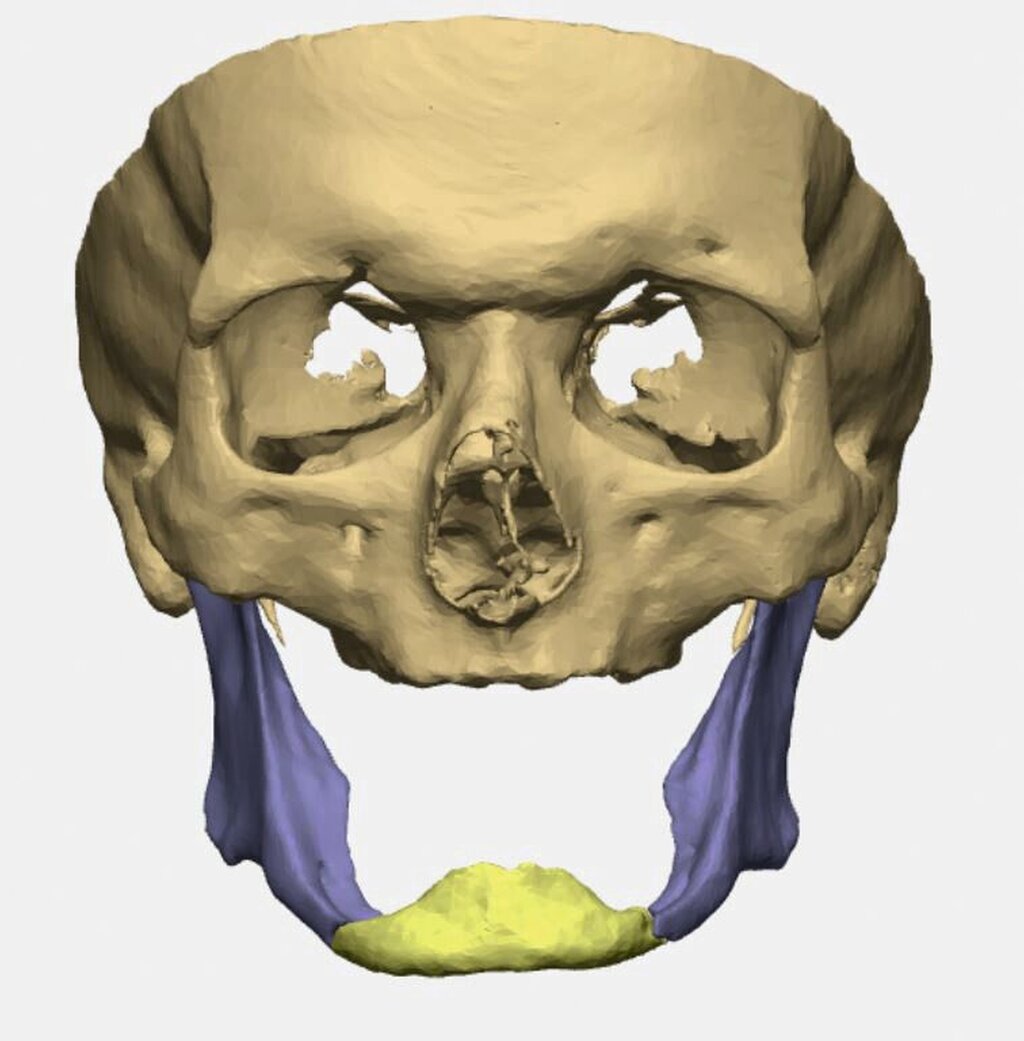

Bei zahnlosem Ober- und Unterkiefer erfolgte die virtuelle Repositionierung des frakturierten Unterkiefers (Abbildung 2a). Mittels CAD/CAM-Verfahren wurde eine stabile Rekonstruktionsplatte aus Titan (patientenspezifisches Implantat; PSI) geplant und hergestellt. Dabei sollte die Position des PSIs im Bereich des Unterkieferkorpus weit kaudal an der Basis sein, so dass später bei der Anpassung einer neuen Unterkieferprothese keine Interferenzen auftreten (Abbildung 2b).

Gleichzeitig konnte durch eine optimierte Bohrlochposition der Nervus alveolaris inferior geschont werden, eine Neurolyse brauchte nicht geplant zu werden. Außerdem wurden an die Zielreposition angepasste Bohrschablonen (drilling guides) hergestellt, die ein Vorbohren der späteren Schraubenlöcher in der exakten Zielposition ermöglichen (Abbildung 2c). In Kombination mit dem PSI sollte so eine Auto-Reposition des Unterkiefers durch die vorgegebenen Bohrlöcher erfolgen.